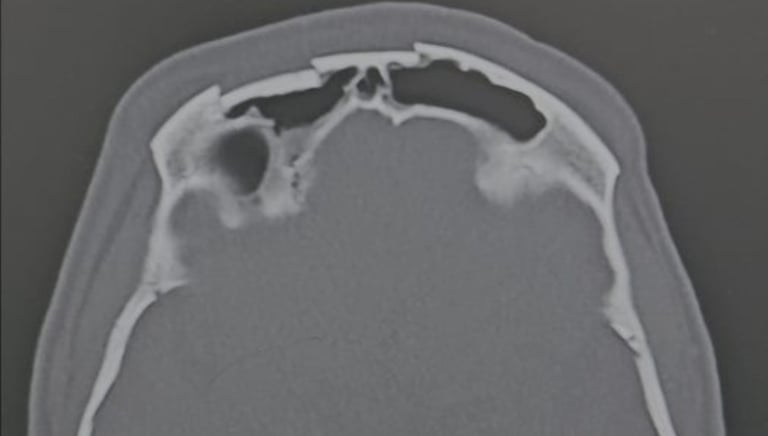

Neurotraumatologia

Tratamos casos diversos relacionados a traumatologia, como hematoma subdural crônico, hematoma subdural agudo, hemicraniectomias descompressivas por causas diversas e afundamentos cranianos abertos e complicações precoces ou tardias, como fístula liquórica, abscesso intracraniano, dentre outros